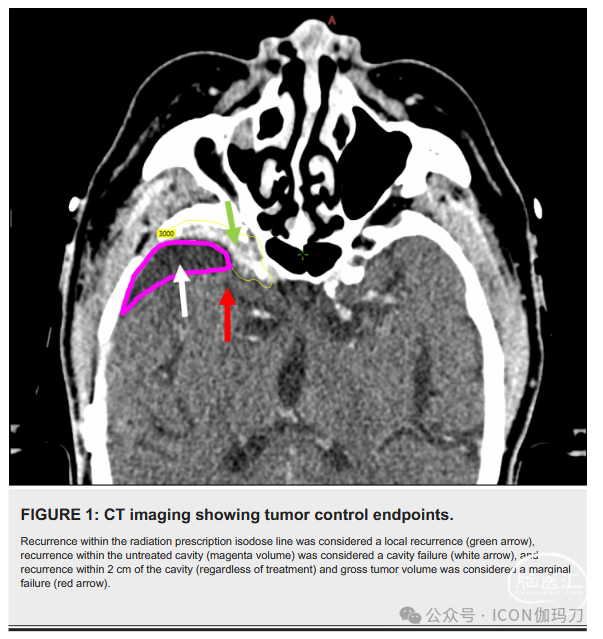

根据RECIST标准,局部复发定义为MRI(或CT,如果MRI有禁忌症)上最大横截直径增加20%,至少有一个体素触及规定的治疗体积或GTR后出现任何新肿瘤。为了评估CTV切缘外扩的作用,边缘复发被定义为在处方体积之外但在切除腔2厘米内的任何新病变。为了评估选择性腔体放疗的影响,腔体复发被定义为在处方体积之外但在切除瘤腔内的任何新病变。在每个病人的基础上确定腔和边缘复发。图1提供了一个患者在没有选择性切除瘤腔(洋红色)的情况下,接受30 Gy治疗的潜在失败分类的例子,分为五次分割(黄色等剂量线)。

图1。CT影像显示肿瘤控制终点。

图1。在放射处方等剂量线内复发被认为是局部复发(绿色箭头),在未治疗的瘤腔内(洋红色体积)复发被认为是腔内失效(白色箭头),在瘤腔(无论治疗)和总肿瘤体积2厘米内复发被认为是边缘失效(红色箭头)。